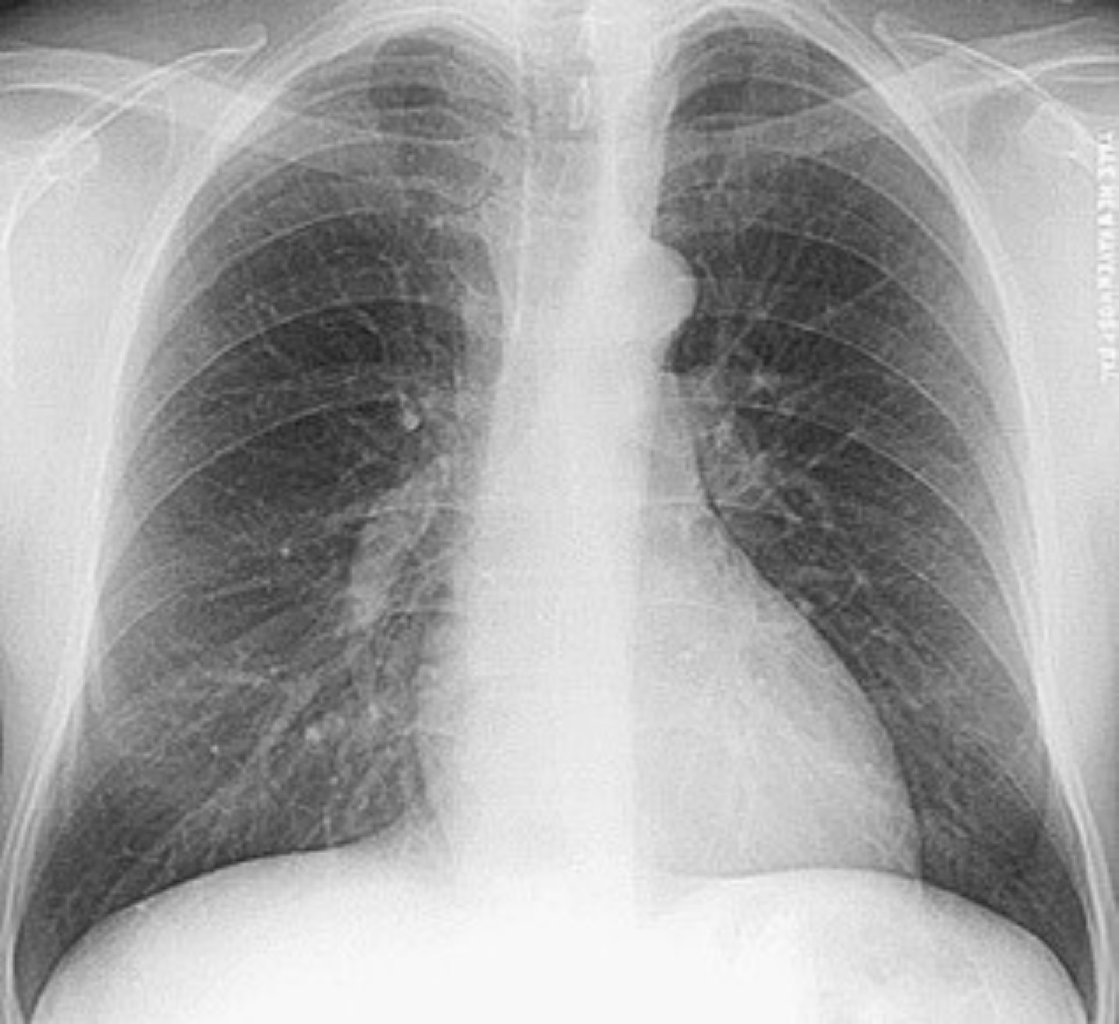

Prosedurun Məqsədi və İstifadəsi Floroskopiyada istifadə olunan rentgen şüaları, sinə qafəsinin i ...